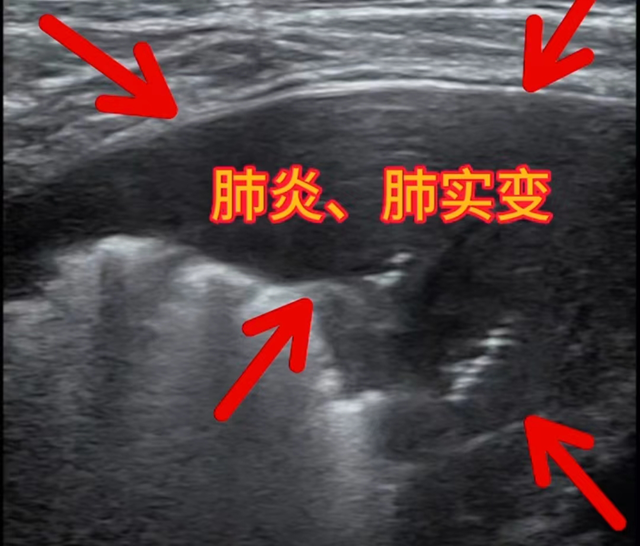

小儿肺超声(肺炎、肺实变病例)

1、肺超声具有无放射损伤、简便、无创,对气胸、肺水肿、肺实变和胸腔积液等疾病的诊断方面具有更高的准确性和敏感性。